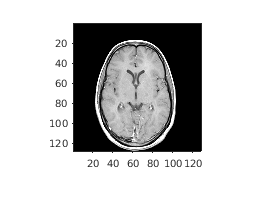

Считайте 3-D объем в рабочую область. Это изображение состоит из 27 систем координат 128 128 пиксельных изображений.

load mri;

D = squeeze(D);

D = ind2gray(D,map);

Создайте imref3d пространственный объект привязки сопоставлен с объемом. В иллюстративных целях обеспечьте пиксельное разрешение в каждой размерности. Разрешение находится в миллиметрах на пиксель.

R = imref3d(size(D),2,2,4)

R =

imref3d with properties:

XWorldLimits: [1 257]

YWorldLimits: [1 257]

ZWorldLimits: [2 110]

ImageSize: [128 128 27]

PixelExtentInWorldX: 2

PixelExtentInWorldY: 2

PixelExtentInWorldZ: 4

ImageExtentInWorldX: 256

ImageExtentInWorldY: 256

ImageExtentInWorldZ: 108

XIntrinsicLimits: [0.5000 128.5000]

YIntrinsicLimits: [0.5000 128.5000]

ZIntrinsicLimits: [0.5000 27.5000]

Отобразите средний срез объема, не использовав пространственный объект привязки. Координаты осей отражают внутренние координаты. Заметьте, что координата (0,0) находится в левом верхнем углу этой плоскости. z=0 является правильным ниже первого среза, и ось z положительна в восходящем направлении к короне головы.

figure

imshow(D(:,:,13))

axis on

Предположим, что вы хотите определить положение, в миллиметрах, функций в этом срезе. Выберите четыре точки выборки и сохраните их внутренние координаты в векторах. Например, первая точка имеет внутренние координаты (54,46,13). Внутренняя z-координата является тем же самым для всех точек в этом срезе.

xI = [54 71 57 70];

yI = [46 48 79 80];

zI = [13 13 13 13];

Преобразуйте внутренние координаты в мировые координаты с помощью intrinsicToWorld.

[xW,yW,zW] = intrinsicToWorld(R,xI,yI,zI)

xW = 1×4

108   142   114   140

yW = 1×4

92    96   158   160

zW = 1×4

52    52    52    52

Итоговые векторы являются миром x-, y-, и z-координатами, в миллиметрах, выбранных точек. Первая точка, например, возмещена от источника на 108 мм в направлении X, 92 мм в направлении Y и 52 мм в z-направлении.